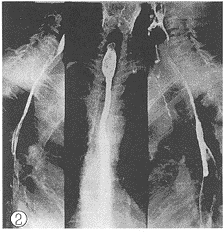

图1 食管上段癌放射治疗后2d摄片,病灶5cm长虫蚀样破坏

图2 放射治疗后14d,病灶消失,柔韧度恢复

2.1 X线影像比较:每例患者在术前加速放射治疗结束后第2d及第14d分别两次摄食管钡餐造影片。由放射科、放射治疗科、胸外科3名副主任医师以上的人员读片,读片前用胶布粘住每例患者的摄片的日期,再进行“多盲法”对比观察、记录。评判标准按1981年第三届全国放射学术会议(郑州)治疗组通过的食管癌放射治疗后X线诊断标准分为4级。Ⅰ级:病变完全消失,食管壁软而光滑,蠕动及扩张良好,粘膜纹理清楚可见(图1、 2);Ⅱ级:病变基本消失,食管壁规则,钡剂能顺利通过,但管壁仍僵直或狭窄,蠕动未恢复,粘膜仍增粗(图3、 4);Ⅲ级:病变明显好转,食管病灶退缩一半以上,没有明显扭曲、成角以及突出腔外的溃疡,稠的钡剂能通过(图5、 6);Ⅳ级:病变残留或恶化,病灶消退不到一半或成角,扭曲明显或有突出腔外的溃疡,钡剂通过极差(图7、 8)。118例术前加速放射治疗后不同时间的X线影像变化结果中,从Ⅲ、Ⅳ级病例上升为Ⅱ、Ⅲ级者最多,分别达 37.8%(17/45)和43.8%(7/16);但未发现越级上升和降级病例。